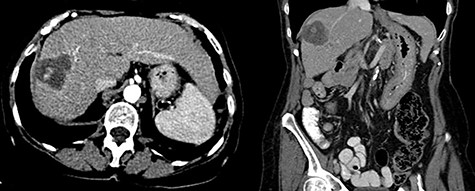

In 2018, the patient had a low dose chest CT for lung cancer screening, given her prior smoking history. The chest CT demonstrated a mass along the right hepatic dome. Triple-phase contrast-enhanced (ce) CT of the abdomen subsequently revealed a large multi-lobulated low-attenuation mass in the right hepatic lobe, predominantly involving Segments V and VIII and, to a lesser extent, Segments VI and VII, measuring 8.8 × 8.3 × 8.2 cm, and associated with a satellite lesion in Segment IVA, measuring 2.2 cm (Fig. 1). A PET CT was ordered and was negative for extrahepatic neoplastic disease.

Abdominal ceCT demonstrated an arterially enhancing mass with early washout characteristic of HCC; venous phase axial and coronal images are featured.